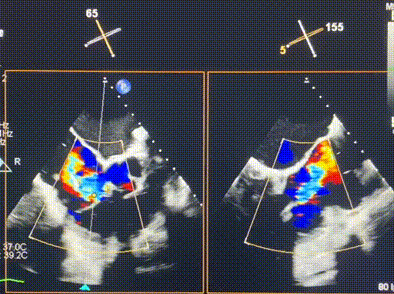

術前超聲提示重度三尖瓣反流

接受本次LuX-Valve Plus治療的是一位三尖瓣重度反流的高齡女性,患者早前曾由于二尖瓣疾病行經導管二尖瓣置換術,植入Tendyne瓣膜一枚,且有ICD植入史。術前CT分析結果顯示,瓣環大小為47.6mm,血管無明顯迂曲和鈣化。由于患者三尖瓣解剖結構復雜,二尖瓣位人工瓣膜造成的超聲偽影和ICD導線的干擾使得歐洲沒有其他合適的商業化和臨床試驗的產品可以對其進行治療。經過Rodrigo Estévez-Loureiro教授團隊的詳盡術前評估,認為LuX-Valve Plus經導管三尖瓣置換系統可以對該患者進行有效的治療。因此,Rodrigo Estévez-Loureiro教授團隊最終決定使用這一中國創新器械為患者進行手術。法國波爾多里爾大學附屬醫院的Thomas Modine教授與加拿大圣保羅醫院的Anson Cheung教授全程線下指導本次手術。